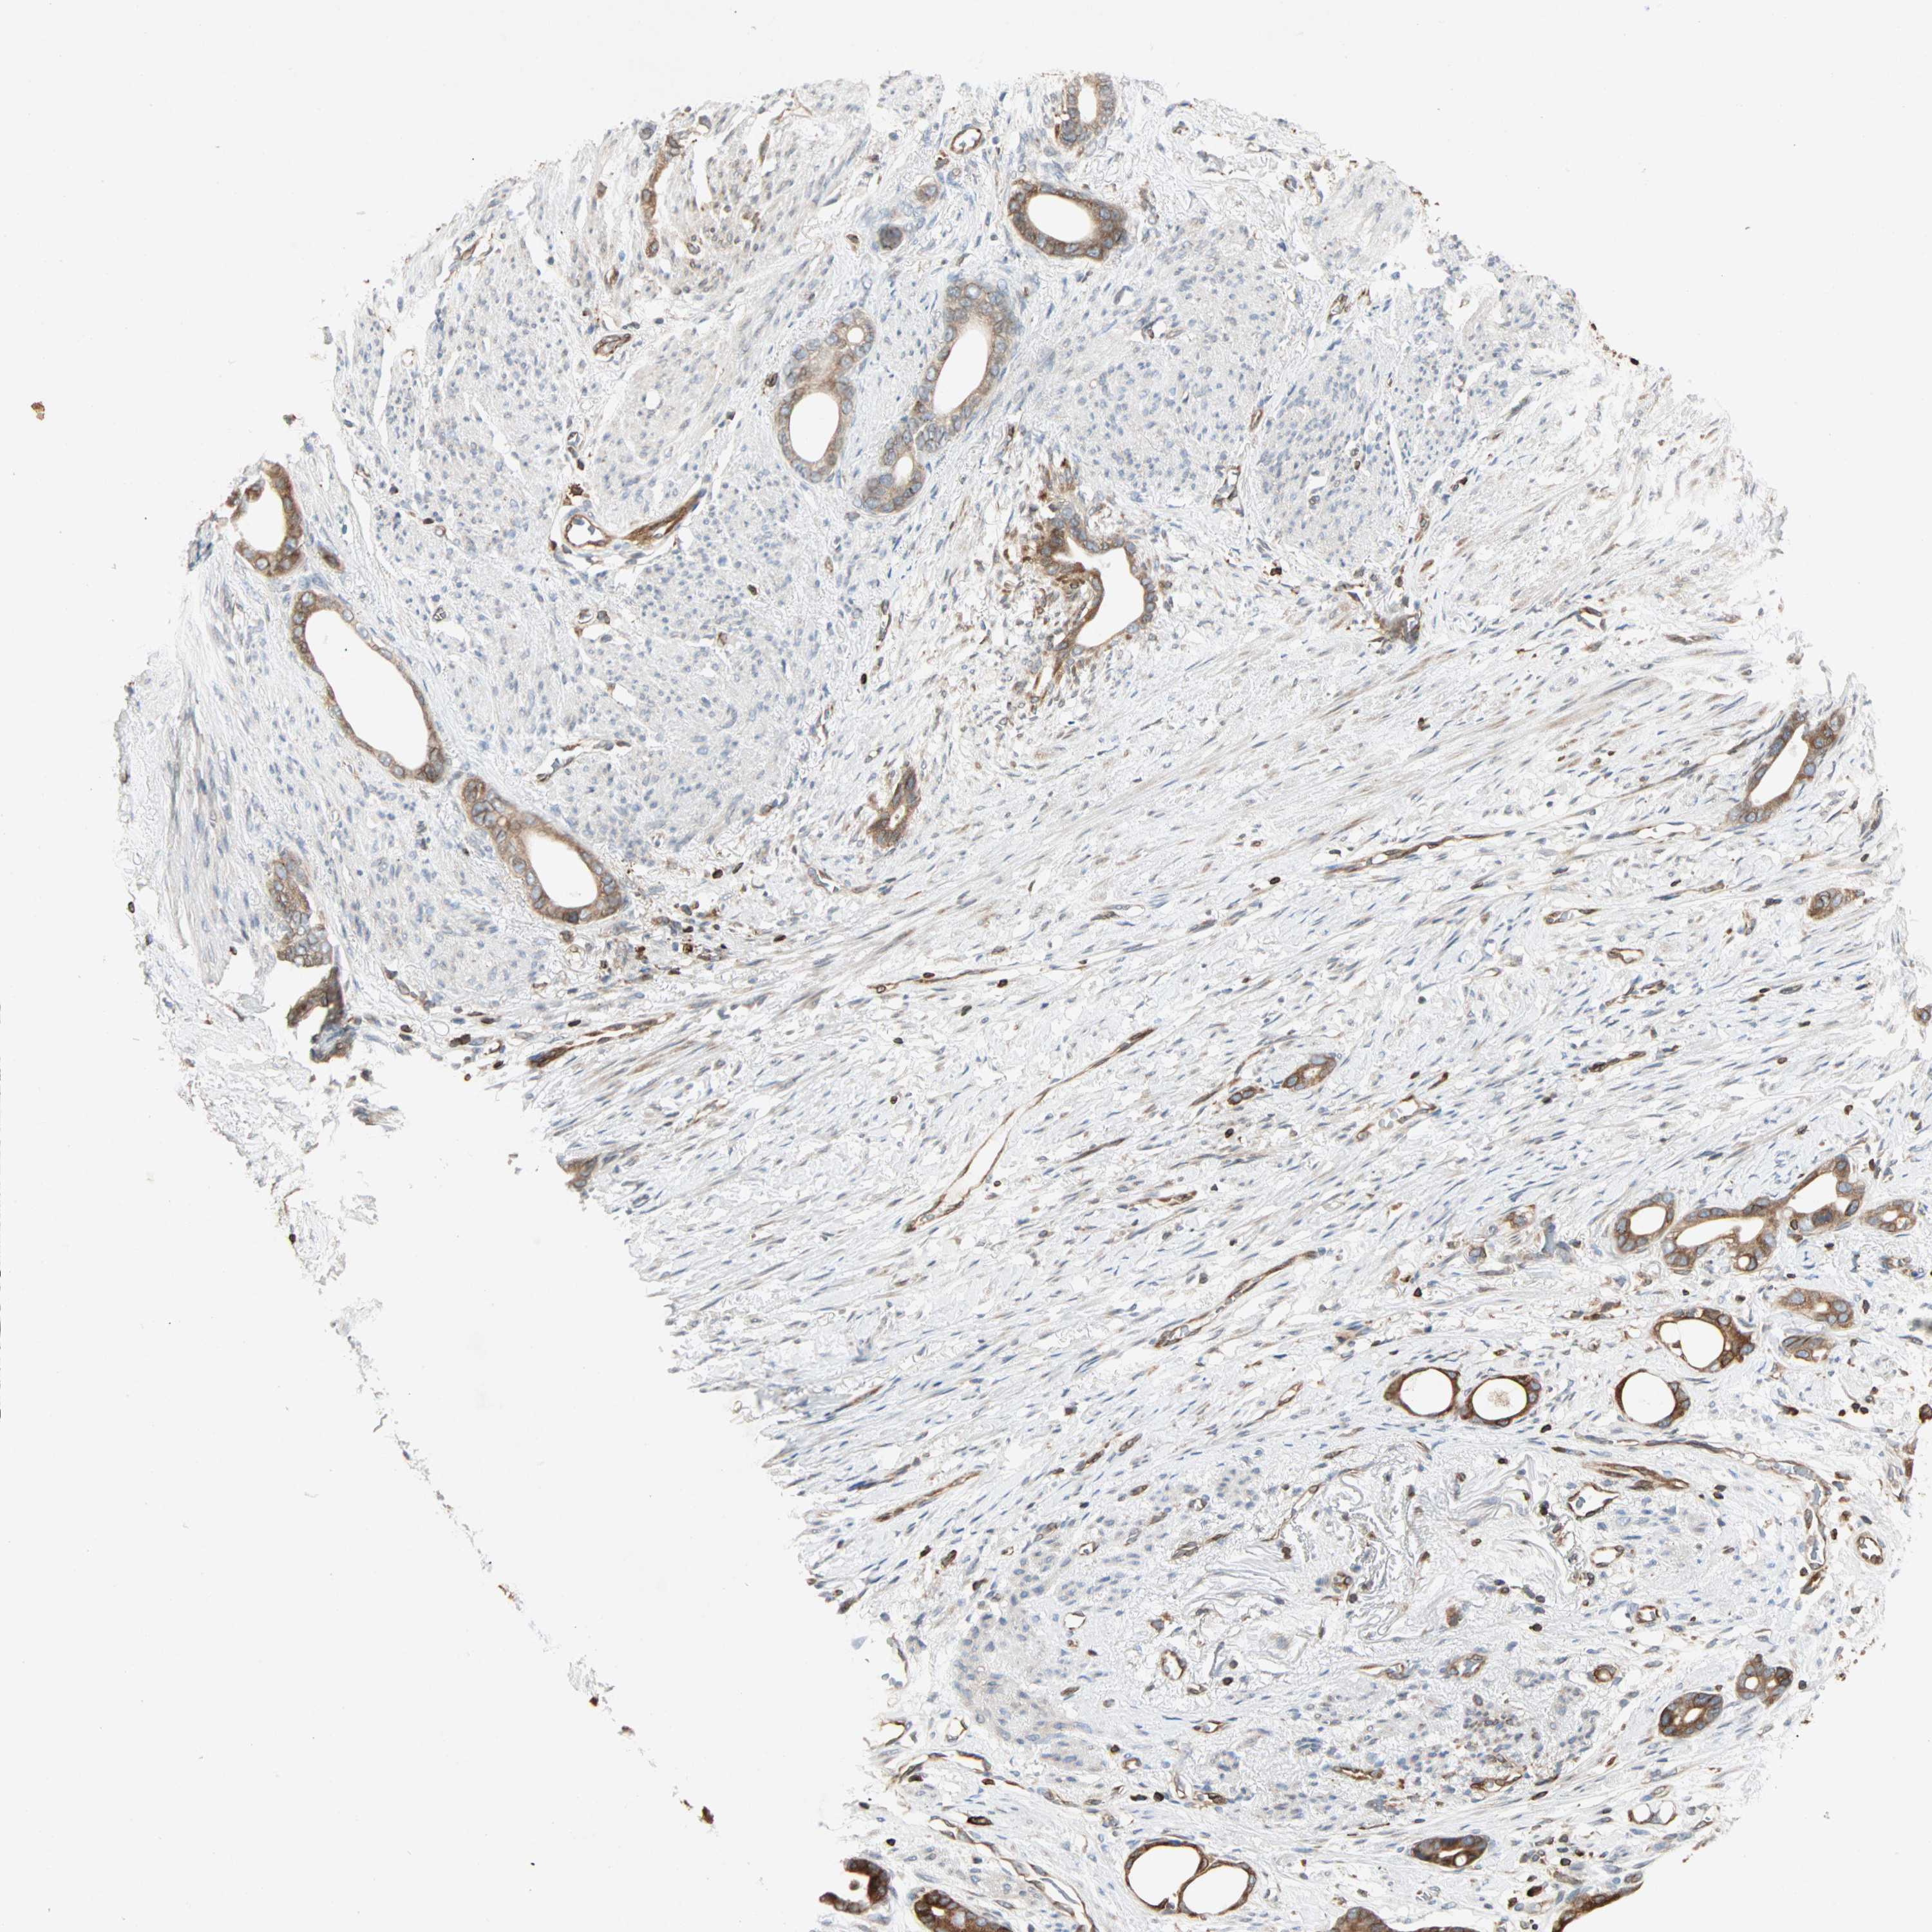

STOMACH CANCER - Protein expressioni

A mouse-over function shows sample information and annotation data. Click on an image to view it in a full screen mode. Samples can be filtered based on level of antibody staining by selecting one or several of the following categories: high, medium, low and not detected. The assay and annotation is described here.

Note that samples used for immunohistochemistry by the Human Protein Atlas do not correspond to samples in the TCGA dataset.

Antibody stainingi

Antibody staining in the annotated cell types in the current human tissue is reported as not detected, low, medium, or high, based on conventional immunohistochemistry profiling in selected tissues. This score is based on the combination of the staining intensity and fraction of stained cells.

Each image is clickable and will lead to virtual microscopy that enables deeper exploration of all samples and also displays staining intensity scores, fraction scores and subcellular localization as well as patient and tissue information for each sample.

Antibody HPA007066

Staining

High

Medium

Low

Not detected

Intensity

Strong

Moderate

Weak

Negative

Quantity

>75%

75%-25%

<25%

None

Location

Nuclear

Cytoplasmic/membranous

Cytoplasmic/membranous,nuclear

Adenocarcinoma, NOS